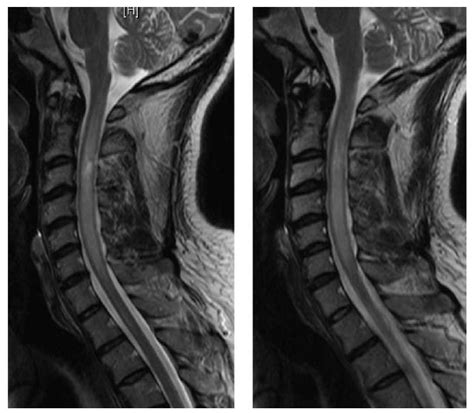

• Imaging Tests: Imaging tests such as X-rays, MRI, or CT scans can provide detailed images of the spinal cord and surrounding structures, helping to identify any abnormalities.